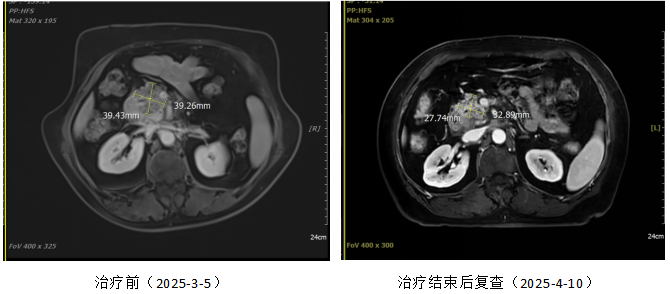

Left image: Before treatment; Right image: One month after treatment.

This case demonstrates the significant efficacy of heavy-ion radiotherapy in the treatment of locally advanced and metastatic pancreatic cancer. Through personalized treatment, the patient exhibited a marked reduction in tumor marker levels and significant imaging improvement.